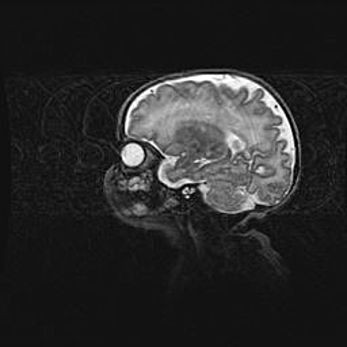

Аномалия Денди-Уокера. Признаки гипоплазии мозолистого тела.

Возраст: 5 месяцев 3 дня

Вес: 5550 г

Пол: мужской

Окружность головы: 39 см

Срок гестации: 40 недель

Аномалия Денди-Уокера – это порок развития головного мозга, для которого характерна триада симптомов: гипотрофия или аплазия червя мозжечка и/или полушарий мозжечка, расширение четвёртого желудочка с формированием ликворной кисты задней черепной ямки, гипертензионная гидроцефалия различной степени.

Гипоплазия мозолистого тела относится к дефектам внутриутробного этапа развития мозговой ткани, возникающим в процессе закладки структур головного мозга, что происходит на начальных этапах развития эмбриона.